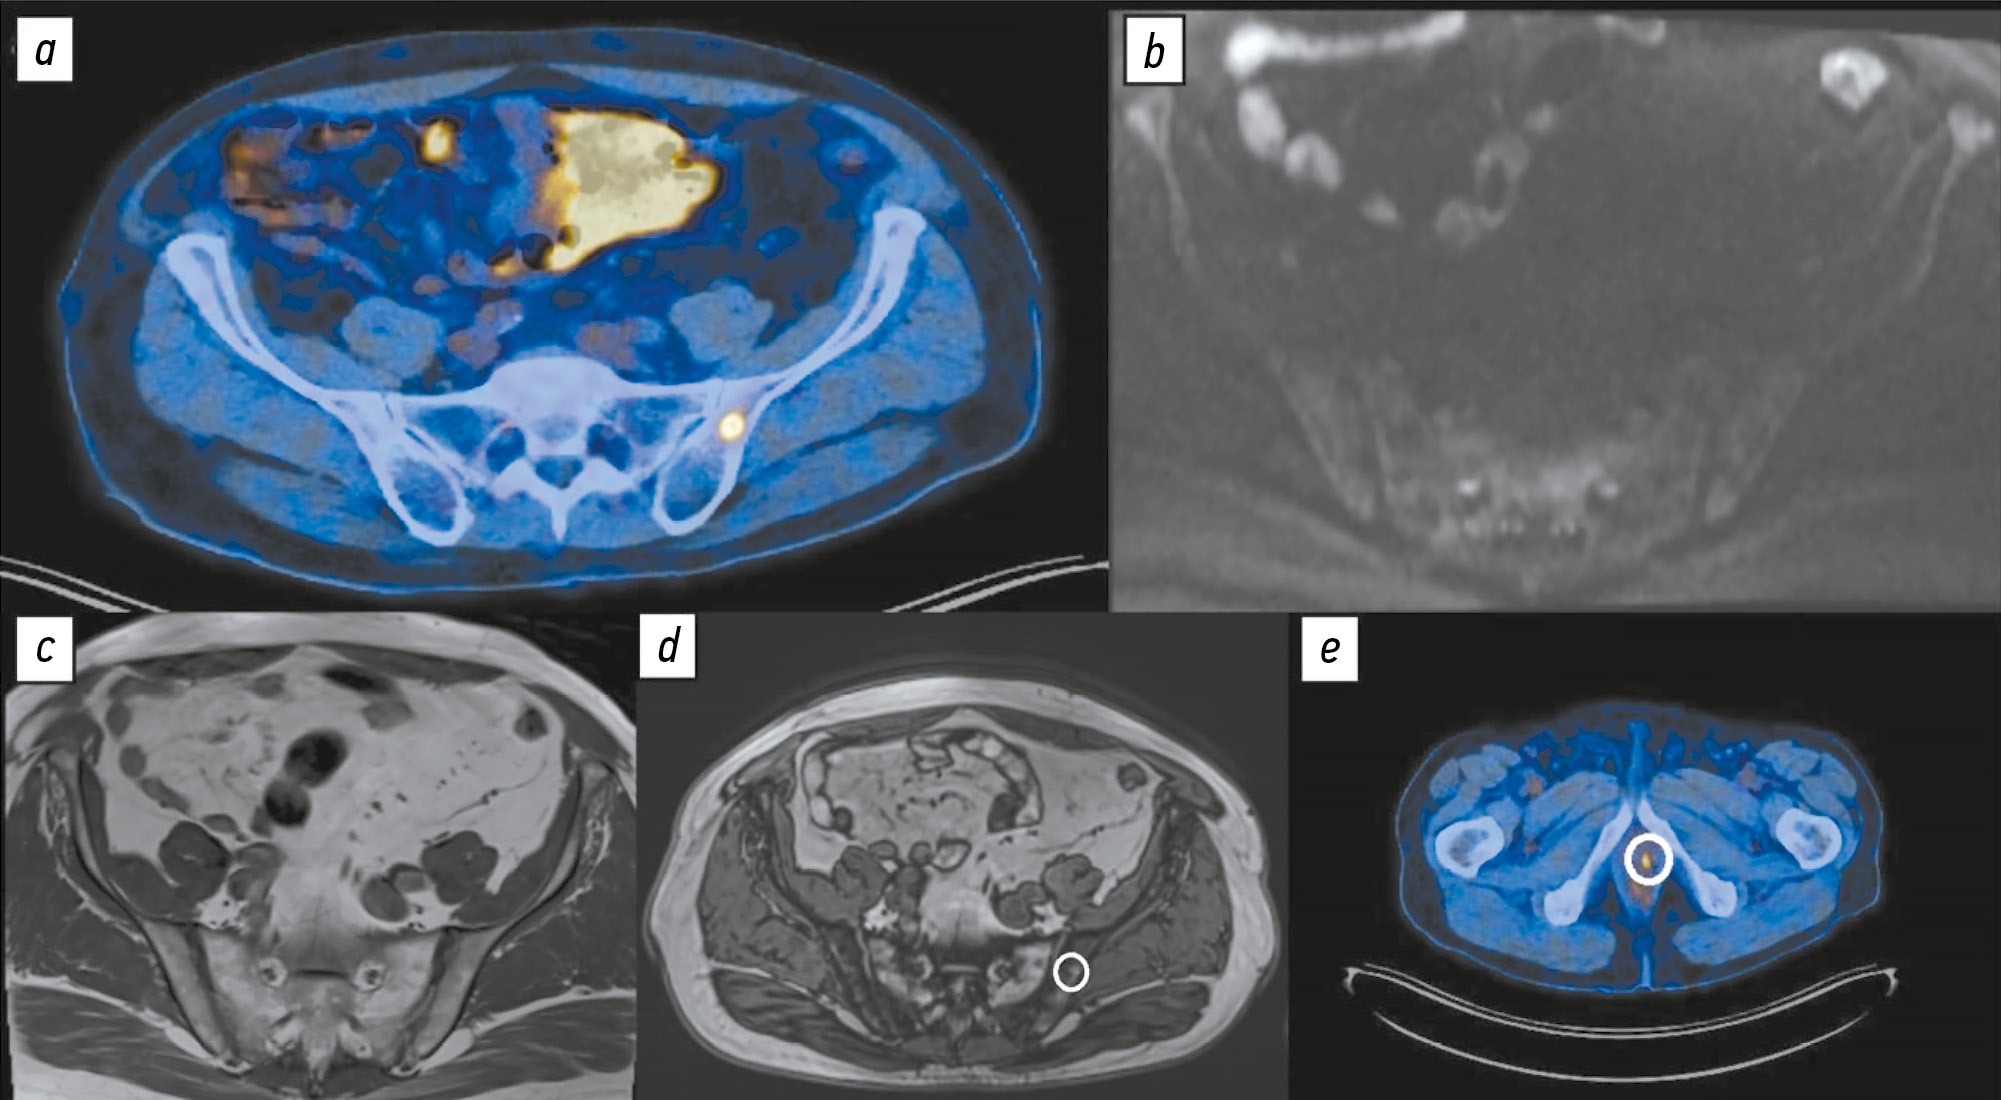

Сравнительная оценка диагностической точности диффузионно-взвешенных изображений всего тела и позитронно-эмиссионной томографии с 18F-простатоспецифичным мембранным антигеном-1007, совмещённой с компьютерной томографией, в выявлении костных метастазов при раке предстательной железы

Аннотация

Обоснование. Повышение доступности 18F-простатоспецифичного мембранного антигена-1007 (18F-ПСМА-1007) для стадирования рака предстательной железы демонстрирует его преимущества, из которых важным является более высокое пространственное разрешение, чем у аналогов. Одновременно накапливаются научные данные, свидетельствующие о значительном увеличении числа ложноположительных находок, преимущественно в костях, что может приводить к необоснованному завышению стадии онкологического процесса. Диффузионно-взвешенные изображения возможно использовать для ранней диагностики метастатического поражения костей.

Цель исследования. Оценка диагностической точности позитронно-эмиссионной томографии всего тела с 18F-ПСМА-1007, совмещённой с компьютерной томографией (ПЭТ/КТ), в сравнении с диффузионно-взвешенными изображениями всего тела и костей малого таза у пациентов с раком предстательной железы.

Методы. Проведено ретроспективное одноцентровое выборочное исследование. Результаты исследований 119 пациентов с раком предстательной железы, разделены на две группы: 1-я группа — 40 пар данных ПЭТ/КТ с 18F-ПСМА-1007 и магнитно-резонансной томографии с диффузионно-взвешенными изображениями всего тела; 2-я группа — 79 пар аналогичных исследований, при этом магнитно-резонансную томографию проводили только в области костей таза. Диагностические исследования выполнены при соблюдении временного интервала между ними не более 14 дней. Осуществляли подсчёт количества выявленных метастатических очагов костей в различных анатомических областях по данным ПЭТ/КТ с 18F-ПСМА-1007 и магнитно-резонансной томографии. Истинно положительными считают очаги, подтверждённые с помощью дополнительных импульсных последовательностей магнитно-резонансной томографии и/или в результате динамического наблюдения.

Результаты. Диффузионно-взвешенная визуализация всего тела продемонстрировала более высокую специфичность в выявлении костных метастазов (58,1%) по сравнению с ПЭТ/КТ с 18F-ПСМА-1007 (51,06%). Однако чувствительность оказалась ниже — 93,22 против 97,55% соответственно.

Заключение. Несмотря на известные преимущества, ПЭТ/КТ с 18F-ПСМА-1007 демонстрирует высокую частоту ложноположительных находок в костях. Наиболее частая их локализация — рёбра, позвонки, кости таза. Для избежания неоправданного завышения стадии рекомендуется проведение уточняющей диагностики подозрительных очагов костей. В качестве такого метода можно использовать магнитно-резонансную томографию всего тела с диффузионно-взвешенными изображениями и селективным подавлением сигнала от жировой ткани.

239-250